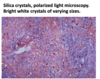

silicosis